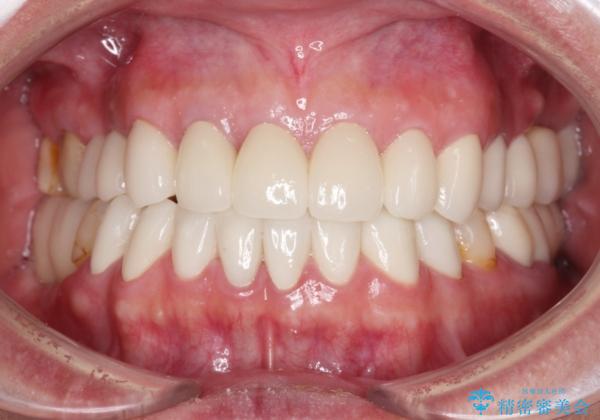

憧れの白い歯に 全顎セラミック治療

- 60歳を越え、黄ばんだ前歯をセラミッククラウンできれいな口元にしたいとのことで来院された患者様です。

診察したところ、前歯は反対咬合であり、その影響で抜歯が必要な奥歯があることが分かりました。

抜歯が必要な奥歯は、インプラント並びにブリッジにより補綴を行い、上下前歯は反対咬合を改善させるように補綴治療を行うこととしました。

健全な歯を削ってセラミッククラウンに置き換えることは、本来避けるべき治療と考えますが、今回は①患者様が60歳を越えていること、②要改善の咬合により抜歯が必要な奥歯があること、③反対咬合の前歯改善の手段としてセラミック治療が選択肢にあることなどから、全顎的なセラミック治療を行うこととしました。